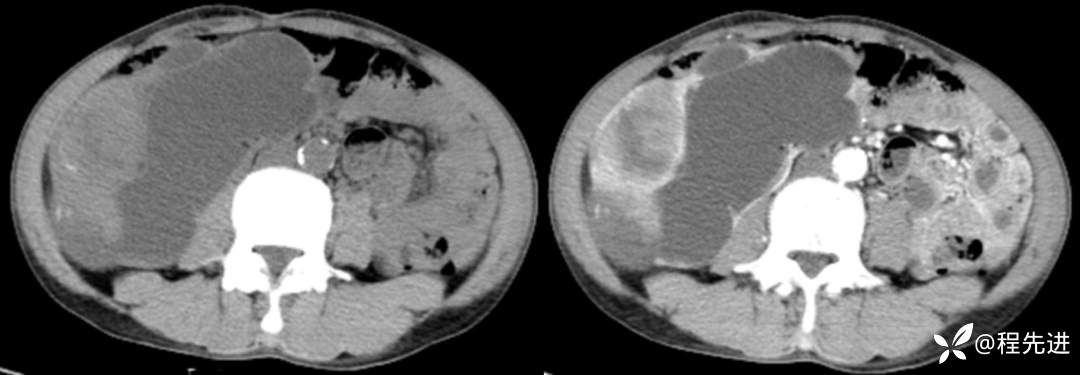

冠状位重建